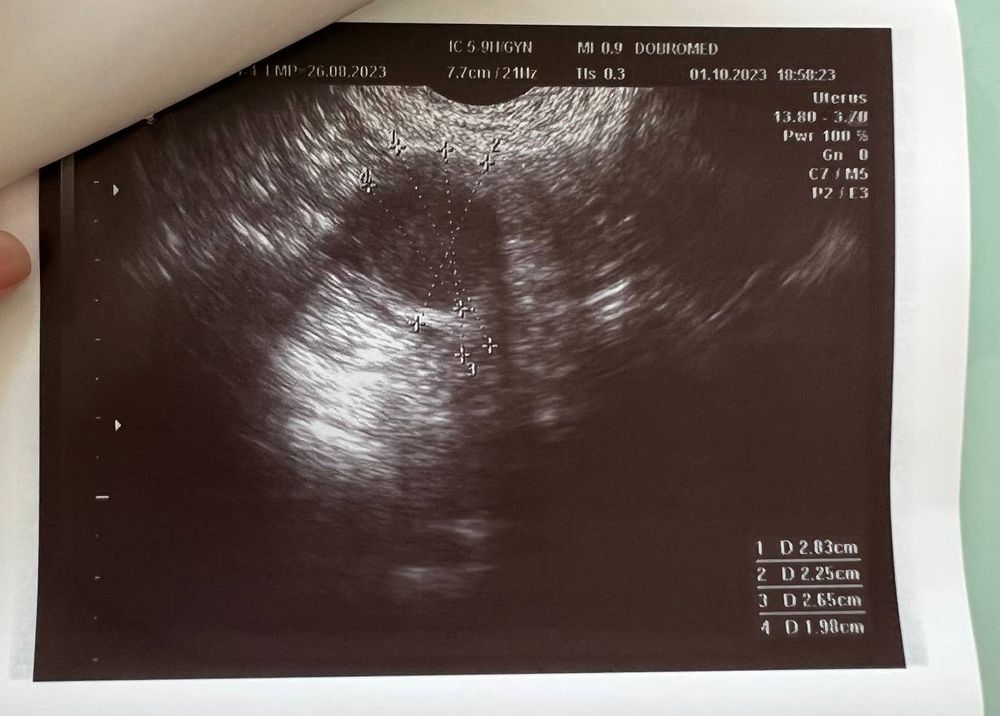

Вчера (1 октября) сходила на УЗИ, беременность подтвердили, маточная.

Размер плодного яйца 4 мм.

Но не видно желтое тело, и мутное содержимое плодного яйца (как она сказала). Меня напугала очень узистка... мол, может быть замершая беременность.

Если есть специалисты тут - пожалуйста, посмотрите снимок

Про мутность в плодном яйце в заключении не сказано. То что нет желточного мешочка, так срок еще маленький, через недельку все должно появиться. Не переживайте. Из тревожного тут только повешенный тонус, и то возможно это реакция на узи датчик. Папаверин повставляйте на ночь до следующего узи. Все должно быть хорошо! 🕊️